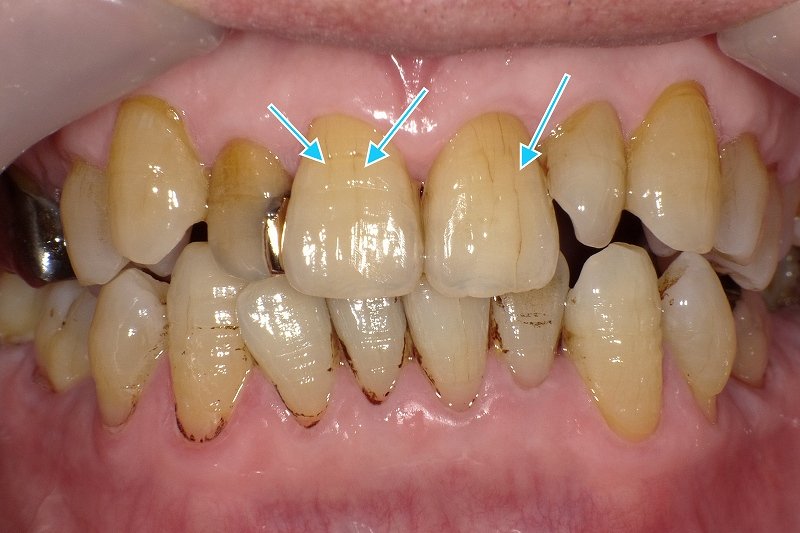

歯茎の変色治療

ブラックマージンやメタルタトゥー、歯茎のメラニン色素沈着など、歯茎の変色にも対応します。自然な歯茎の色を取り戻すことで、より美しい笑顔を実現します。

歯茎下がりの治療

歯茎下がりの治療も行っており、歯肉を健康で美しい状態に保つお手伝いをいたします。